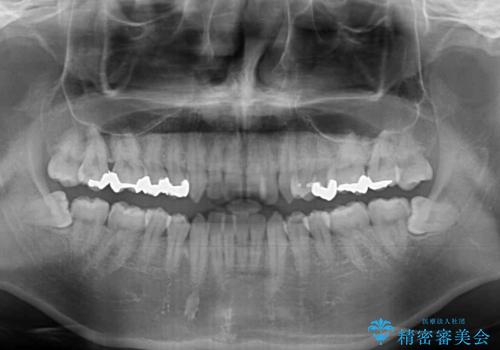

前歯のクロスバイト インビザラインによる矯正治療

- 上下のクロスバイトと前歯のデコボコを気にして来院された患者様です。

インビザラインを用い、IPR(歯と歯の間を削る)と歯列全体を拡大させることで、歯並びを整えていくこととしました。